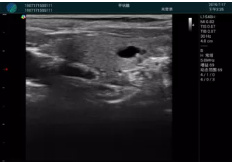

清晰顯示孕囊,通過軟件包計算孕齡7w+6d

M20實時引導,術(shù)中清晰顯示孕囊被破壞和抽吸針的過程,清晰顯示吸引針

抽吸結(jié)束后縱切子宮,孕囊已被完全抽吸,未見明顯殘留

橫切子宮,發(fā)現(xiàn)右側(cè)宮腔靠近宮角處有少許脫模樣殘留

M20引導下,抽吸針找到右側(cè)宮角處再次清掃

二次抽吸后再次進行超聲檢查,宮腔未見殘留,宮腔線清晰顯示